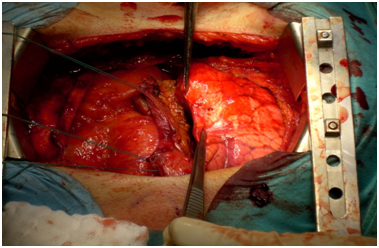

Laboratory examination showed a low haemoglobin level while the other values were in normal rage. Four hours after admission the patient developed more chest pain, respiratory fatigue and became hypotensive. Emergency surgical exploration was decided and performed with median sternotomy. After sternotomy and heart exploration 300 ml bloody pericardial effusion could be extracted. A perforation was found in the middle of the right atrium from the lateral side, with the dislocated lead perforating the pericardium and causing a right lung penetration (Figures 35). The lead was pulled out of the right atrium about 10 cm and cut off. After invagination of the cut off atrial lead in the right atrium the perforated atrium was sewn using a purse-string suture (Prolene 5x0 BB). After opening and exploration of the right pleura 300 ml fixed haematoma and 700 ml bloody pleural effusion were extracted. Subtle inspection of the right lung and sewing of the injury was performed. Chest closure was then performed after placement of two drainage tubes, one retro - cardiac and one right pleural (Figure 6). The patient had a normal recovery without any complications. The patient was discharged after eight days and was planned for a later atrial lead implantation in the future.

Figure 3 Perforation of the right atrium with the right atrial lead.

Figure 4 Perforation of the right lateral side of the pericard.

Figure 5 Penetration of the right lung before sewing.